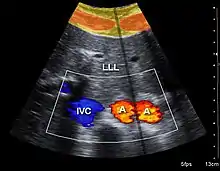

Both abdominal and endoanal ultrasound are frequently used in gastroenterology and colorectal surgery. In abdominal sonography, the major organs of the abdomen such as the pancreas, aorta, inferior vena cava, liver, gall bladder, bile ducts, kidneys, and spleen may be imaged. However, sound waves may be blocked by gas in the bowel and attenuated to differing degrees by fat, sometimes limiting diagnostic capabilities. The appendix can sometimes be seen when inflamed (e.g.: appendicitis) and ultrasound is the initial imaging choice, avoiding radiation if possible, although it frequently needs to be followed by other imaging methods such as CT. Endoanal ultrasound is used particularly in the investigation of anorectal symptoms such as fecal incontinence or obstructed defecation. It images the immediate perianal anatomy and is able to detect occult defects such as tearing of the anal sphincter. Ultrasonography of liver tumors allows for both detection and characterization.[13]

Compression is used in this ultrasonograph to get closer to the abdominal aorta, making the superior mesenteric vein and the inferior vena cava look rather flat.